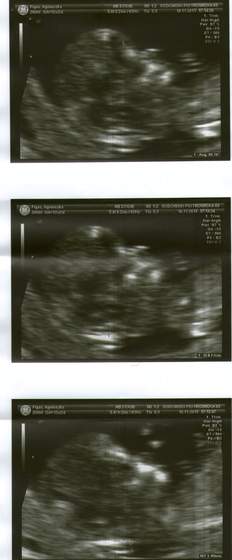

))) oczywiście to nieinwazyjne ;**** ja moze juz dzisiaj też wkleje wam fotki mojej małej Kruszynki

Agagu wklejaj zdjecia bo juz sie doczekac nie moge!

super zdjecia Agagu,az zazdroszcze takich dokladnych!!!nie to co moje rozmazane!super fotki

i gratuluje coreczki!!